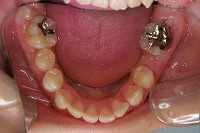

下顎 | ![]() |

反対咬合と前歯が生えてこない事を主訴に来院された、10歳4か月の男の子です。診断「下顎骨の過成長による骨格性反対咬合で上顎正中の左方偏位と埋伏歯を伴う」1期治療で反対咬合の解消と埋まっていた前歯を牽引しました。